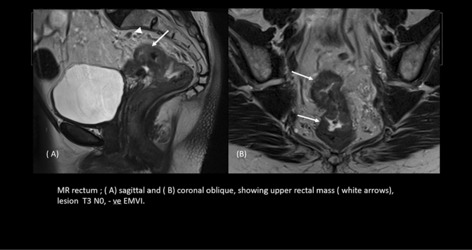

Colorectal—Malignant

O193—The role of 3D modelling technology in recognition of colorectal tumour deposits

Aims: 3D modelling technology is rapidly gaining interest in various fields of surgery. It can be used for operative planning and navigation, as well as surgical education and patient interaction. It allows for depiction of complex anatomical relationships in a more comprehensible way than traditional radiological images. However, it also has potential to become a tool facilitating gaining further understanding of surgical pathology by allowing to display and analyse imaging data in a new way. Tumour deposits are a challenging entity. They are currently being closely investigated with an aim to develop understanding of their role in colorectal cancer spread. It is an ever evolving concept which requires further research to fully appreciate the origin and significance of tumour deposits. We applied the novel 3D modelling technology to illustrate tumour deposits in colorectal cancer.

Methods: 3D virtual models were created through manual segmentation of CT and MRI scans obtained according to protocols routinely used in colorectal cancer staging. No extra patient time or preparation were needed. CT and MRI images were analysed by Gastrointestinal Radiologist to delineate the tumour and provide the cancer staging. Manual segmentation was then performed in 3D Slicer, an open-source, free software used for creation of three-dimensional anatomical models. Additional post-processing was applied in MeshLab or Blender.

Results: Ten 3D models depicting tumour deposits in colorectal cancer were created. Models of right- and left-sided bowel cancer with tumour deposits were derived from CT scans, while those of rectal cancer—from MRI scans. 3D models depicted bowel with the tumour and tumour deposits, relevant vasculature and lymph nodes, as well as surrounding structures as required. Models can be manipulated to allow for most comprehensible inspection of different anatomical structures and relationships. The transparency of each structure can be changed. The morphological appearance of tumour deposits and their relation to vessels can be readily appreciated. The morphological differences between the tumour deposits and lymph nodes, both benign and metastatic, can also be evaluated.

Conclusions: This work follows on from our previous experience with exploration of 3D modelling technology to map tumour deposits in rectal cancer, based on rectal MRI images. This innovative technology shows a huge potential to enhance our understanding of surgical pathology. It can provide a welcome assistance in exploring new concepts and developing new theories. It can facilitate communication and discussion around the evolving concepts. It is a versatile novel tool which can be successfully applied for depiction of tumour deposits in any part of the bowel. Here we showed its feasibility for the use in left- and right-sided bowel cancer, in addition to previously explored rectal cancer. It can utilise modalities commonly used in colorectal cancer staging – CT and MRI, which renders it clinically applicable. While there is an ongoing debate on the correct classification of tumour deposits and their full significance in metastatic process, as well as their prognostic value, 3D technology can facilitate familarisation with their appearance. It can also become an educational tool both for radiologists and surgeons and a valuable adjunct in the multidisciplinary management of colorectal cancer.